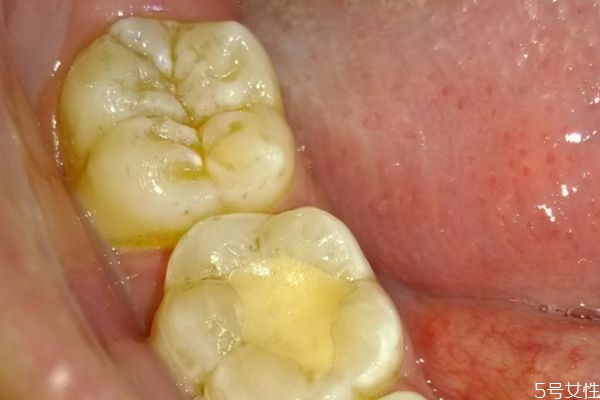

牙齦腫痛的絕大部分原因,還是牙結(jié)石或者說是軟垢的刺激。牙齒表面不干凈,軟垢以及結(jié)石的堆積,就會刺激這個牙齦,刺激牙齦的血管擴(kuò)張,然后牙齦就會紅腫出現(xiàn)疼痛,經(jīng)常發(fā)生牙齦腫痛,必須要到醫(yī)院來進(jìn)行檢查。針對具體的情況,進(jìn)行具體的處理。如果是軟垢或者結(jié)石的刺激影響,那么主要的治療方法,還是進(jìn)行洗牙潔牙,或者說是超聲波潔治,如果長期出現(xiàn)牙齦腫痛,不處理的話病人一般會自己,第一次自己很難受,然后第二呢牙齦出血,也會對你的社交造成一些困擾。第三長期的牙齦腫痛,牙齒的炎癥得不到有效的控制,會使牙槽骨以及牙齦萎縮,那么牙齒會松動,牙齒松動以后,一般來說絕大部分情況,沒有辦法再恢復(fù)正常,會造成牙齒脫落。

牙齦腫的危害性是特別嚴(yán)重的,對于患者的牙齦健康損害嚴(yán)重,病發(fā)期間給患者帶來了困擾,甚至?xí)蓴_到工作以及生活,提醒各位朋友需要將牙齦腫了解透徹,平時的生活中多了解相關(guān)的誘發(fā)起因,生活中誘發(fā)牙齦腫的起因特別的復(fù)雜,主要包括牙周膿腫、牙齦膿腫、智齒冠周炎、根尖周炎等,這是都是常見的病因,很多人會因?yàn)檫@些病癥而出現(xiàn)牙齦腫痛的癥狀,從而侵害了牙齒及牙齦部位的健康。如果患者自身存在牙齦或者是牙周組織方面的慢性炎癥,特別是患者的機(jī)體抵抗力嚴(yán)重下降、天氣干燥、進(jìn)食辛辣及刺激性嚴(yán)重的食物時,都會導(dǎo)致原有的慢性炎癥產(chǎn)生急性的發(fā)作,繼而誘發(fā)了牙齦腫痛的癥狀,傷害了患者的牙齦健康,為此朋友們要注意口腔的衛(wèi)生,正確的刷牙,還要注意提早做一些牙齦腫痛的預(yù)防工作,這樣才能減輕牙齦腫的病發(fā)率,從而保護(hù)了人們的牙齦健康,遠(yuǎn)離了疾病的困擾和損害。